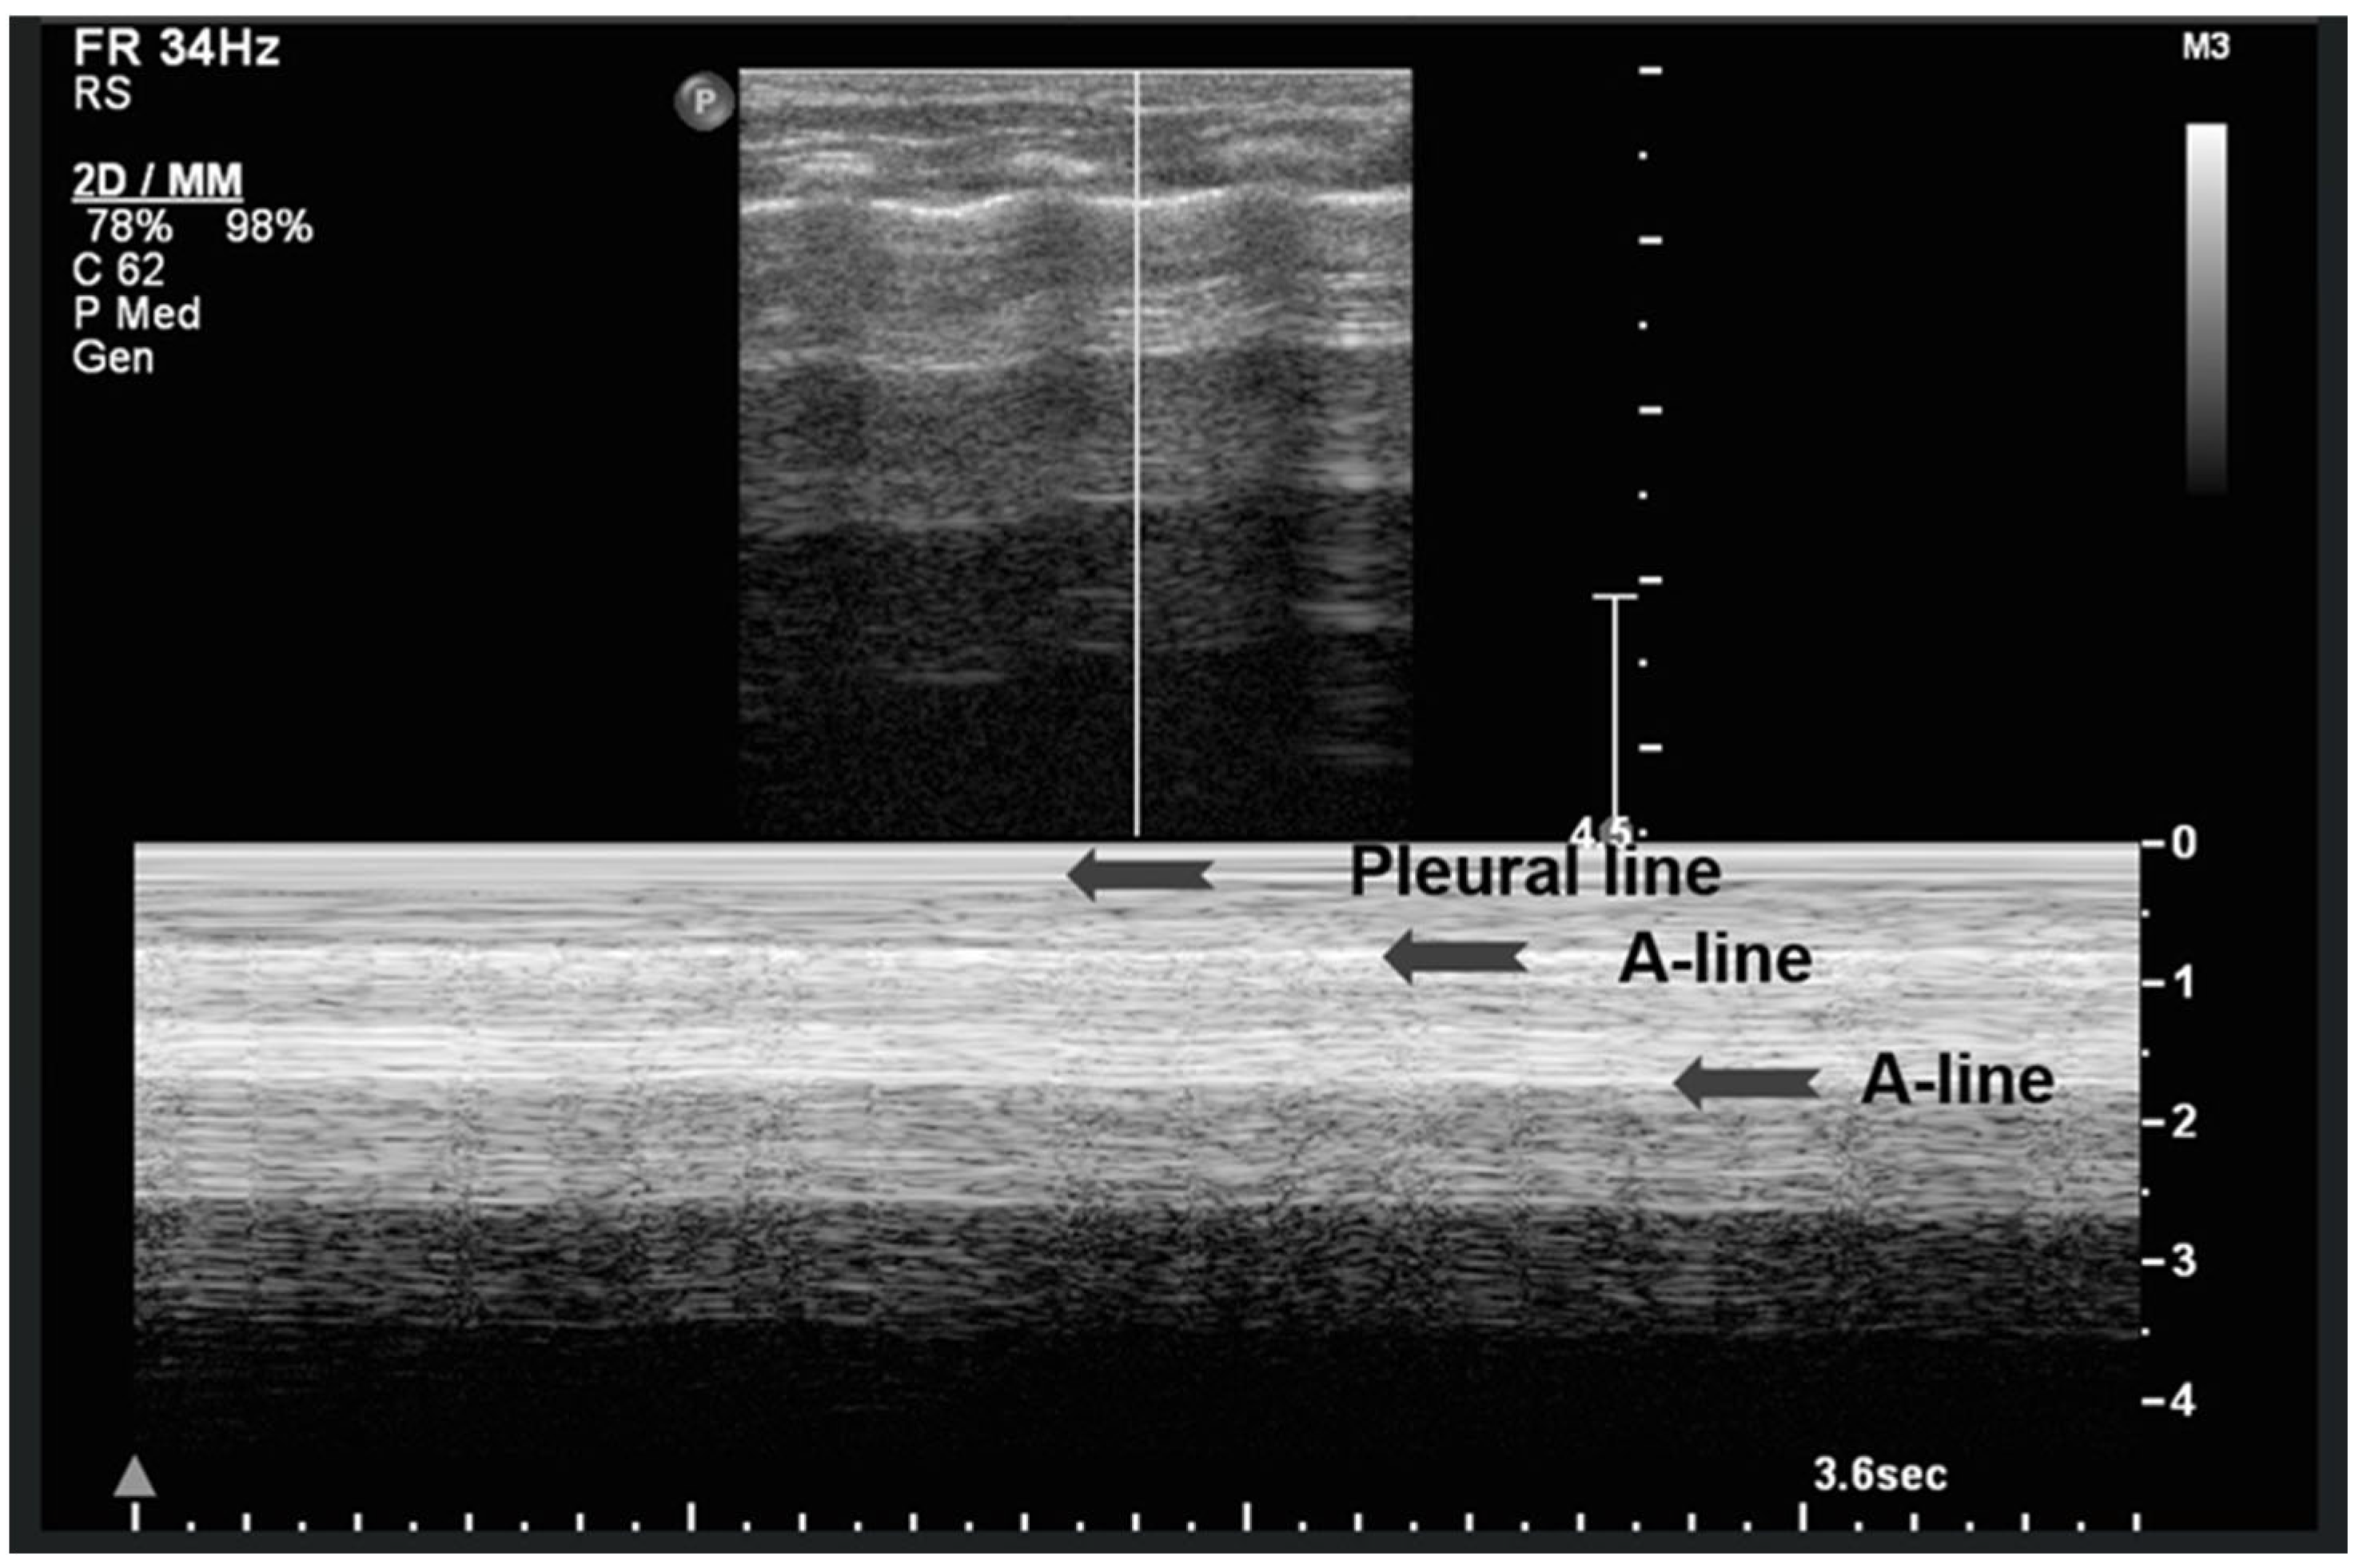

3.1.5. Sea-Shore Sign

The “sea-shore sign” is a characteristic ultrasound finding observed during M-mode (motion mode) scanning, and is indicative of normal lung sliding. In this pattern, the pleural line and overlying chest wall structures produce a series of horizontal echogenic lines, representing static tissues (Figure 6).

Figure 6.

Upper image: LUS with normal A-Lines in B (bright)-mode. The simultaneous M (motion)-mode image (lower image) reveals series of horizontal echogenic lines which represent the pleural line and its reverberations (A-lines), as well as the air-filled alveoli with a granular/sandy appearance (more prominent in real time scan). These in combination produce the seashore sign.

In contrast, the underlying lung parenchyma, which moves in synch with respiration, generates a granular or sandy appearance due to the dynamic motion of air-filled alveoli [17]. This combination creates the visual effect of waves (static layers) above and sand (with a dynamic speckled texture) below, thus producing the so-called “sea-shore sign”. The presence of this sign confirms normal apposition and movement of the visceral and parietal pleurae, and can be used to effectively rule out pneumothorax at the examination site. The “sea-shore sign” is considered to be a reliable and non-invasive indicator of intact lung sliding, and is frequently used in both adult and neonatal lung ultrasound to assess respiratory function and pleural integrity [5,6,15,22,23].

When this sign is absent, uniform horizontal straight lines, known as the stratosphere sign or “barcode sign”, appear, indicating pneumothorax as a possible cause [18,24].